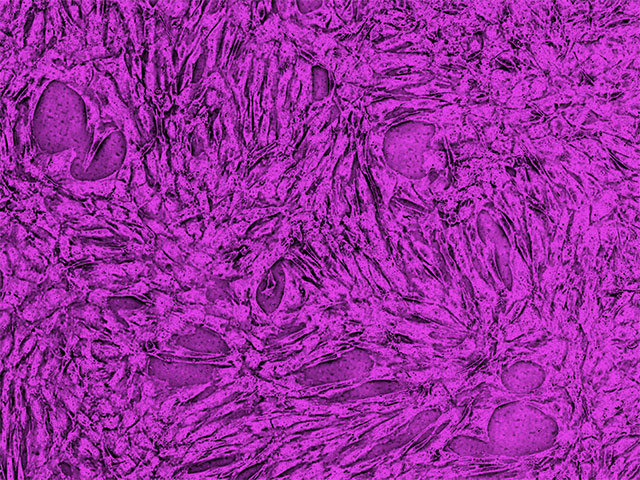

The shear forces, pressure drops, and clogged nozzles that cells encounter inside conventional electrostatic-droplet cell sorters damage cells, alter their morphology and growth curves, decrease viability, and may even affect cellular genetics. For example, HeLa cells experience a shallower growth curve than normal after cell sorting.

These collective forces are called “sorter-induced cellular stress (SICS)”.[2] SICS is particularly troublesome for delicate cells such as transfected cells, cardiomyocytes, hepatocytes, sperm cells, adipocytes, and induced pluripotent stem cells (iPSCs) and their products.